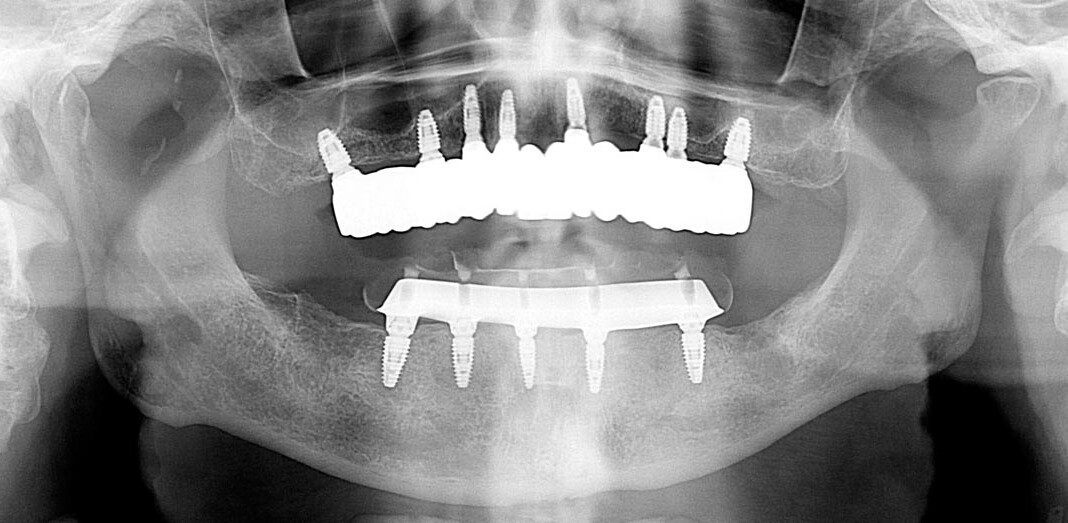

Pre-op, Panoramic x-ray. Note: Excellent bone in the upper front, reasonably good bone everywhere else.

Lower teeth extracted, some bone removal lower, 8 upper implants, 5 lower implants, lower immediate temporary bridge.